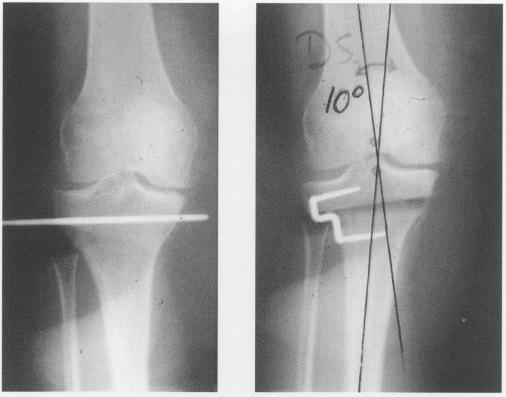

Proximal tibial osteotomy (PTO) as a surgical treatment for selected cases of unicompartmental knee joint arthritis has been performed by the author since 1970. The results of the first 113 cases were reported in October, 1978, at the Iowa Orthopaedic Society meeting. The study was continued through 1995 to include a total of 279 osteotomies in 230 patients. Each operation was performed by the author using the surgical technique as described by Coventry. Postoperative rehabilitation and follow-up remained constant throughout the 25 year period. A detailed retrospective review of all clinical records was undertaken to determine the long term results of PTO, using revision to total knee replacement or death as end points. Eighty-three patients died and 19 were lost to follow-up. A questionnaire regarding pain, function, and the necessity of further surgery was sent to the remainder. Each patient was contacted and invited back for a clinical evaluation and radiographs. At an average 13 year follow-up, 116 patients (42%) had no symptoms and were considered a good result. This long-term review revealed that, with strict adherence to the surgical principles of obtaining and maintaining proper alignment, proximal tibial osteotomy for unicompartmental arthritis can result in good function and symptomatic relief for an average of ten to 14 years.